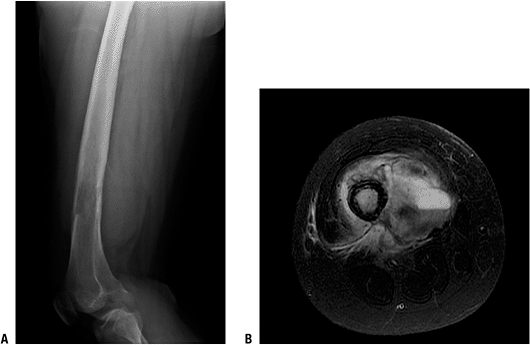

Figure 6.1-6 A 16-year-old girl with 5-month history of thigh pain. (A)

Lateral radiograph shows a radiolucent, permeative lesion of the distal diaphysis of the femur. There is a Codman’s triangle superiorly, and the large soft tissue extension can be seen posterior to the femur. Note the lack of ossification radiographically within the lesion and soft tissue extension. (B) T2-weighted, fat-suppressed axial image through the femur at the level of the lesion reveals a large soft tissue mass and fluid–fluid level within the mass. Biopsy of this lesion confirmed a telangiectatic osteosarcoma. |

0.4% to 12% of all osteosarcomas

-

Typically a permeative, destructive radiolucent lesion with little if any bone production (see Fig. 6.1-6)

Can be confused radiographically with aneurysmal bone cyst or giant cell tumor of bone